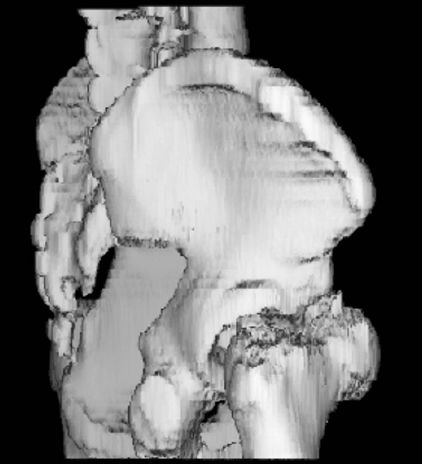

胫骨平台骨折

疼痛科怎么理疗疼痛科医生、康复理疗科医生、针刀针灸医生应掌握的常见骨科疾病X光片_https://www.jmylbn.com_新闻资讯_第35张